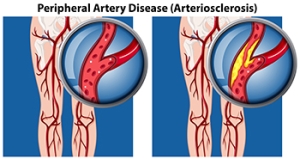

How Peripheral Artery Disease Can Affect the Feet

Peripheral artery disease, abbreviated PAD, also referred to as peripheral vascular disease, is a condition that arises from the reduced flow of blood to the body’s extremities, including the lower legs and feet. People with diabetes are more susceptible to developing PAD, as a result of weakened and damaged blood vessels from having high blood sugar. Blood clot formation within the vessels can also contribute to this condition. Conditions such as arthritis, which causes inflammation of the arteries, can further fuel peripheral artery disease. Other factors, such as smoking, hypertension, and obesity, increase the risk of developing PAD. Symptoms can include intermittent pain, coldness, numbness, and a bluish hue in the skin. In more advanced stages, wounds that resist healing, and areas of skin that blacken may develop due to the lack of adequate blood flow. In such cases, swift medical intervention is extremely important. If you suspect you may have peripheral artery disease that is affecting your lower extremities, it is suggested that you make an appointment with a podiatrist, who is specifically trained to manage this condition.

Peripheral artery disease can pose a serious risk to your health. It can increase the risk of stroke and heart attack. If you have symptoms of peripheral artery disease, consult with one of our podiatrists from James Kutchback, DPM, CWS-P. Our doctors will assess your condition and provide you with quality foot and ankle treatment.

Peripheral artery disease (PAD) is when arteries are constricted due to plaque (fatty deposits) build-up. This results in less blood flow to the legs and other extremities. The main cause of PAD is atherosclerosis, in which plaque builds up in the arteries.

Peripheral Artery Disease

Peripheral artery disease (PAD), or peripheral arterial disease, is a circulatory problem in which there is a reduction of blood flow to the limbs due to narrowed arteries. When peripheral artery disease develops, the extremities do not receive enough blood flow; this may cause symptoms to develop such as claudication, or leg pain when walking. The legs are the most common site of peripheral artery disease.

Claudication, or leg pain when walking, is one of several symptoms that can develop due to peripheral artery disease. Other symptoms caused by the disease include painful cramping in the hips, thighs, or calves after certain activities; leg numbness or weakness; coldness in the lower leg or foot; sores on the lower extremities that do not heal; hair loss on the lower extremities; and a missing or weak pulse in the lower extremities. In more severe cases, pain may even occur when the body is at rest or when lying down.

Peripheral artery disease is typically caused by atherosclerosis, a condition in which fatty deposits build up in the arterial walls and reduce blood flow. Smoking, diabetes, obesity, high blood pressure, and high cholesterol are some of the risk factors for peripheral artery disease.

If you are experiencing pain, numbness, or other symptoms in the lower extremities, see your healthcare professional immediately. Diagnosed peripheral artery disease can be treated with various medications, angioplasty and surgery, exercise programs, or alternative medicine. It is important to consult a healthcare professional to determine the best treatment for you.